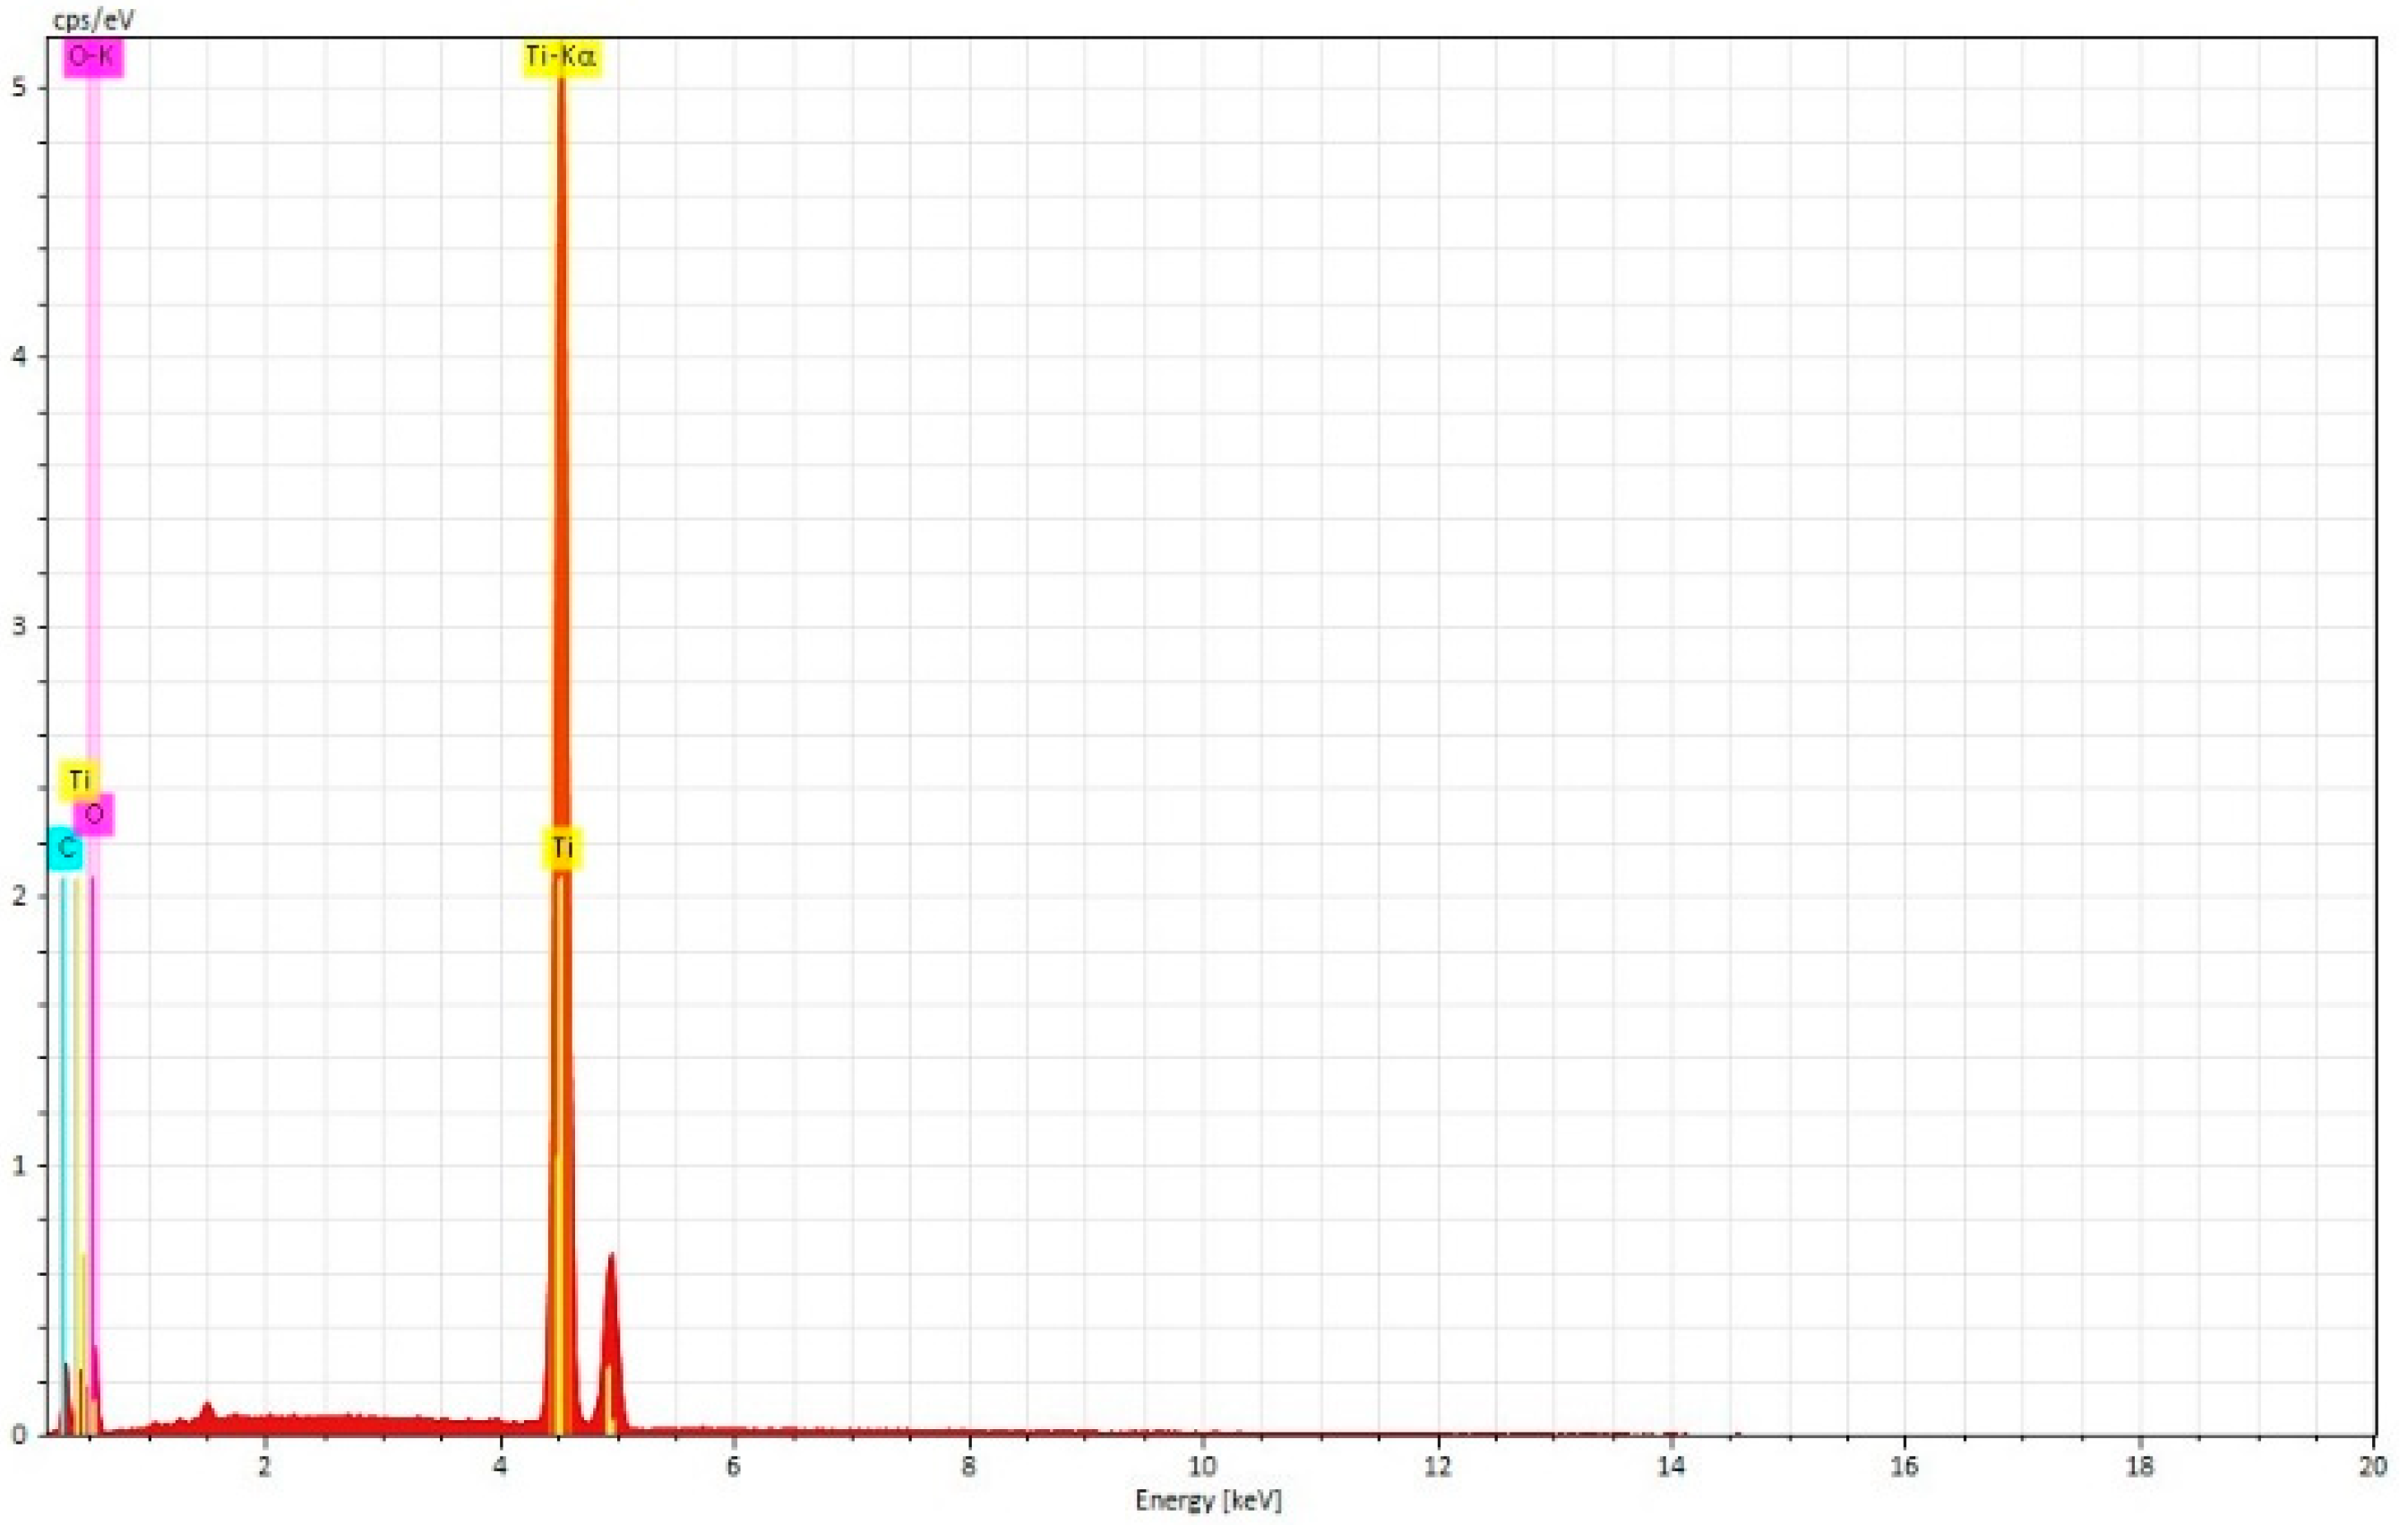

3.2. Scanning Electron Microscopy-EDS Analysis

3.2.2. Used and Sterilized Drill and Conical Tapper